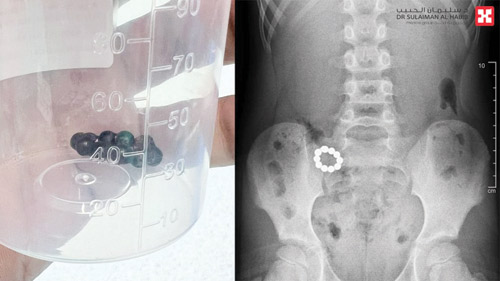

ذكر ذلك د.عبدالله عبدالدائم، استشاري جراحة الأطفال وحديثي الولادة، رئيس الفريق الطبي المعالج، وقال إن الطفل أُسعف إلى المستشفى وهو يعاني من إعياء شديد وآلام حادة بالبطن، مصحوبة بنوبات متكررة من القيء، وفور وصوله خضع لفحوصات دقيقة ومنها الأشعة السينية والتصوير المقطعي المحوسب وأظهرت أن الأجسام الغريبة هي «10» كرات مغناطيسية وتسببت بفعل خاصية التجاذب والتنافر في حدوث تلف وثقوب في جدار المعدة والقولون.

وأضاف د. عبدالله عبدالدائم أن الفريق الطبي أجرى للطفل عملية عاجلة باستخدام المنظار الجراحي لإزالة الكرات ومعالجة الثقوب الناتجة عن التجاذب المغناطيسي واستئصال الجزء التالف من الأمعاء وإعادة توصيل الأجزاء السليمة، من خلال فتحة جراحية صغيرة، واستمرت العملية لنحو «4» ساعات، وتكللت ولله الحمد بالنجاح التام، ودون أية مضاعفات، ونقل الطفل وهو في حالة مستقرة إلى العناية المركزة حيث أمضى «48» ساعة، ومن ثم حُول إلى غرفة التنويم، وتحسنت حالته، وبدأ في تناول الطعام بشكل تدريجي، وغادر المستشفى بعد «5» أيام وهو بصحة ممتازة، واستعاد لاحقاً نمط حياته الطبيعية.